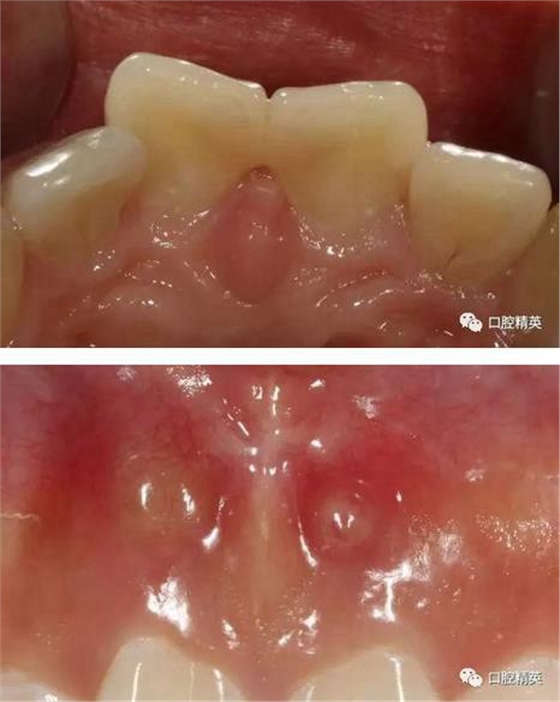

檢查:11,21近中鄰面可見(jiàn)樹(shù)脂類充填體,兩牙唇側(cè)根尖部有膿包狀突起,觸診疼痛,11,21無(wú)松動(dòng),叩診稍有不適,冷熱診檢查無(wú)反應(yīng),X-ray示11,21充填體底部近髓,根尖區(qū)無(wú)明顯異常影像。

(四診)11,21唇側(cè)膿腫基本消除,叩(-),預(yù)備樁道,置入纖維樁,備牙,取模,翻制臨時(shí)冠。

有一點(diǎn)不足之處在于齦緣的高低不完全一致,補(bǔ)救辦法同上——激光輕掃